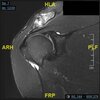

A 22-year-old professional baseball catcher has posterior shoulder pain and severe external rotation weakness with the arm in adduction. Radiographs are normal. MRI scans are shown in Figures 1 through 3. Management should consist of

arthroscopic repair and decompression. The MRI scans reveal a large posterior paralabral cyst associated with a posterior-superior labral tear. The cyst appears as a well-defined, smoothly marginated mass with low signal intensity on T1-weighted MRI scans and with high signal intensity on T2-weighted MRI scans. MRI also reveals changes in the supraspinatus and infraspinatus muscles secondary to denervation, including decreased muscle bulk and fatty infiltration. MRI has the added advantage, compared with other imaging modalities, of detecting intra-articular lesions, such as labral tears, which are frequently associated with ganglion cysts of the shoulder. In this case of a professional baseball player with a space-occupying lesion causing nerve compression with an associated labral tear, the treatment of choice is arthroscopic decompression of the cyst and repair of the tear.